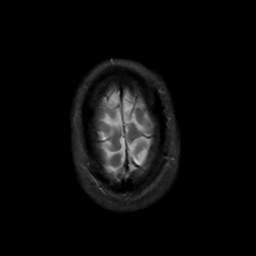

MR Study #6, March 17, 1991 -- Slice #46

[Home][Help][Clinical][Tour 1][Tour 2] Slice 46